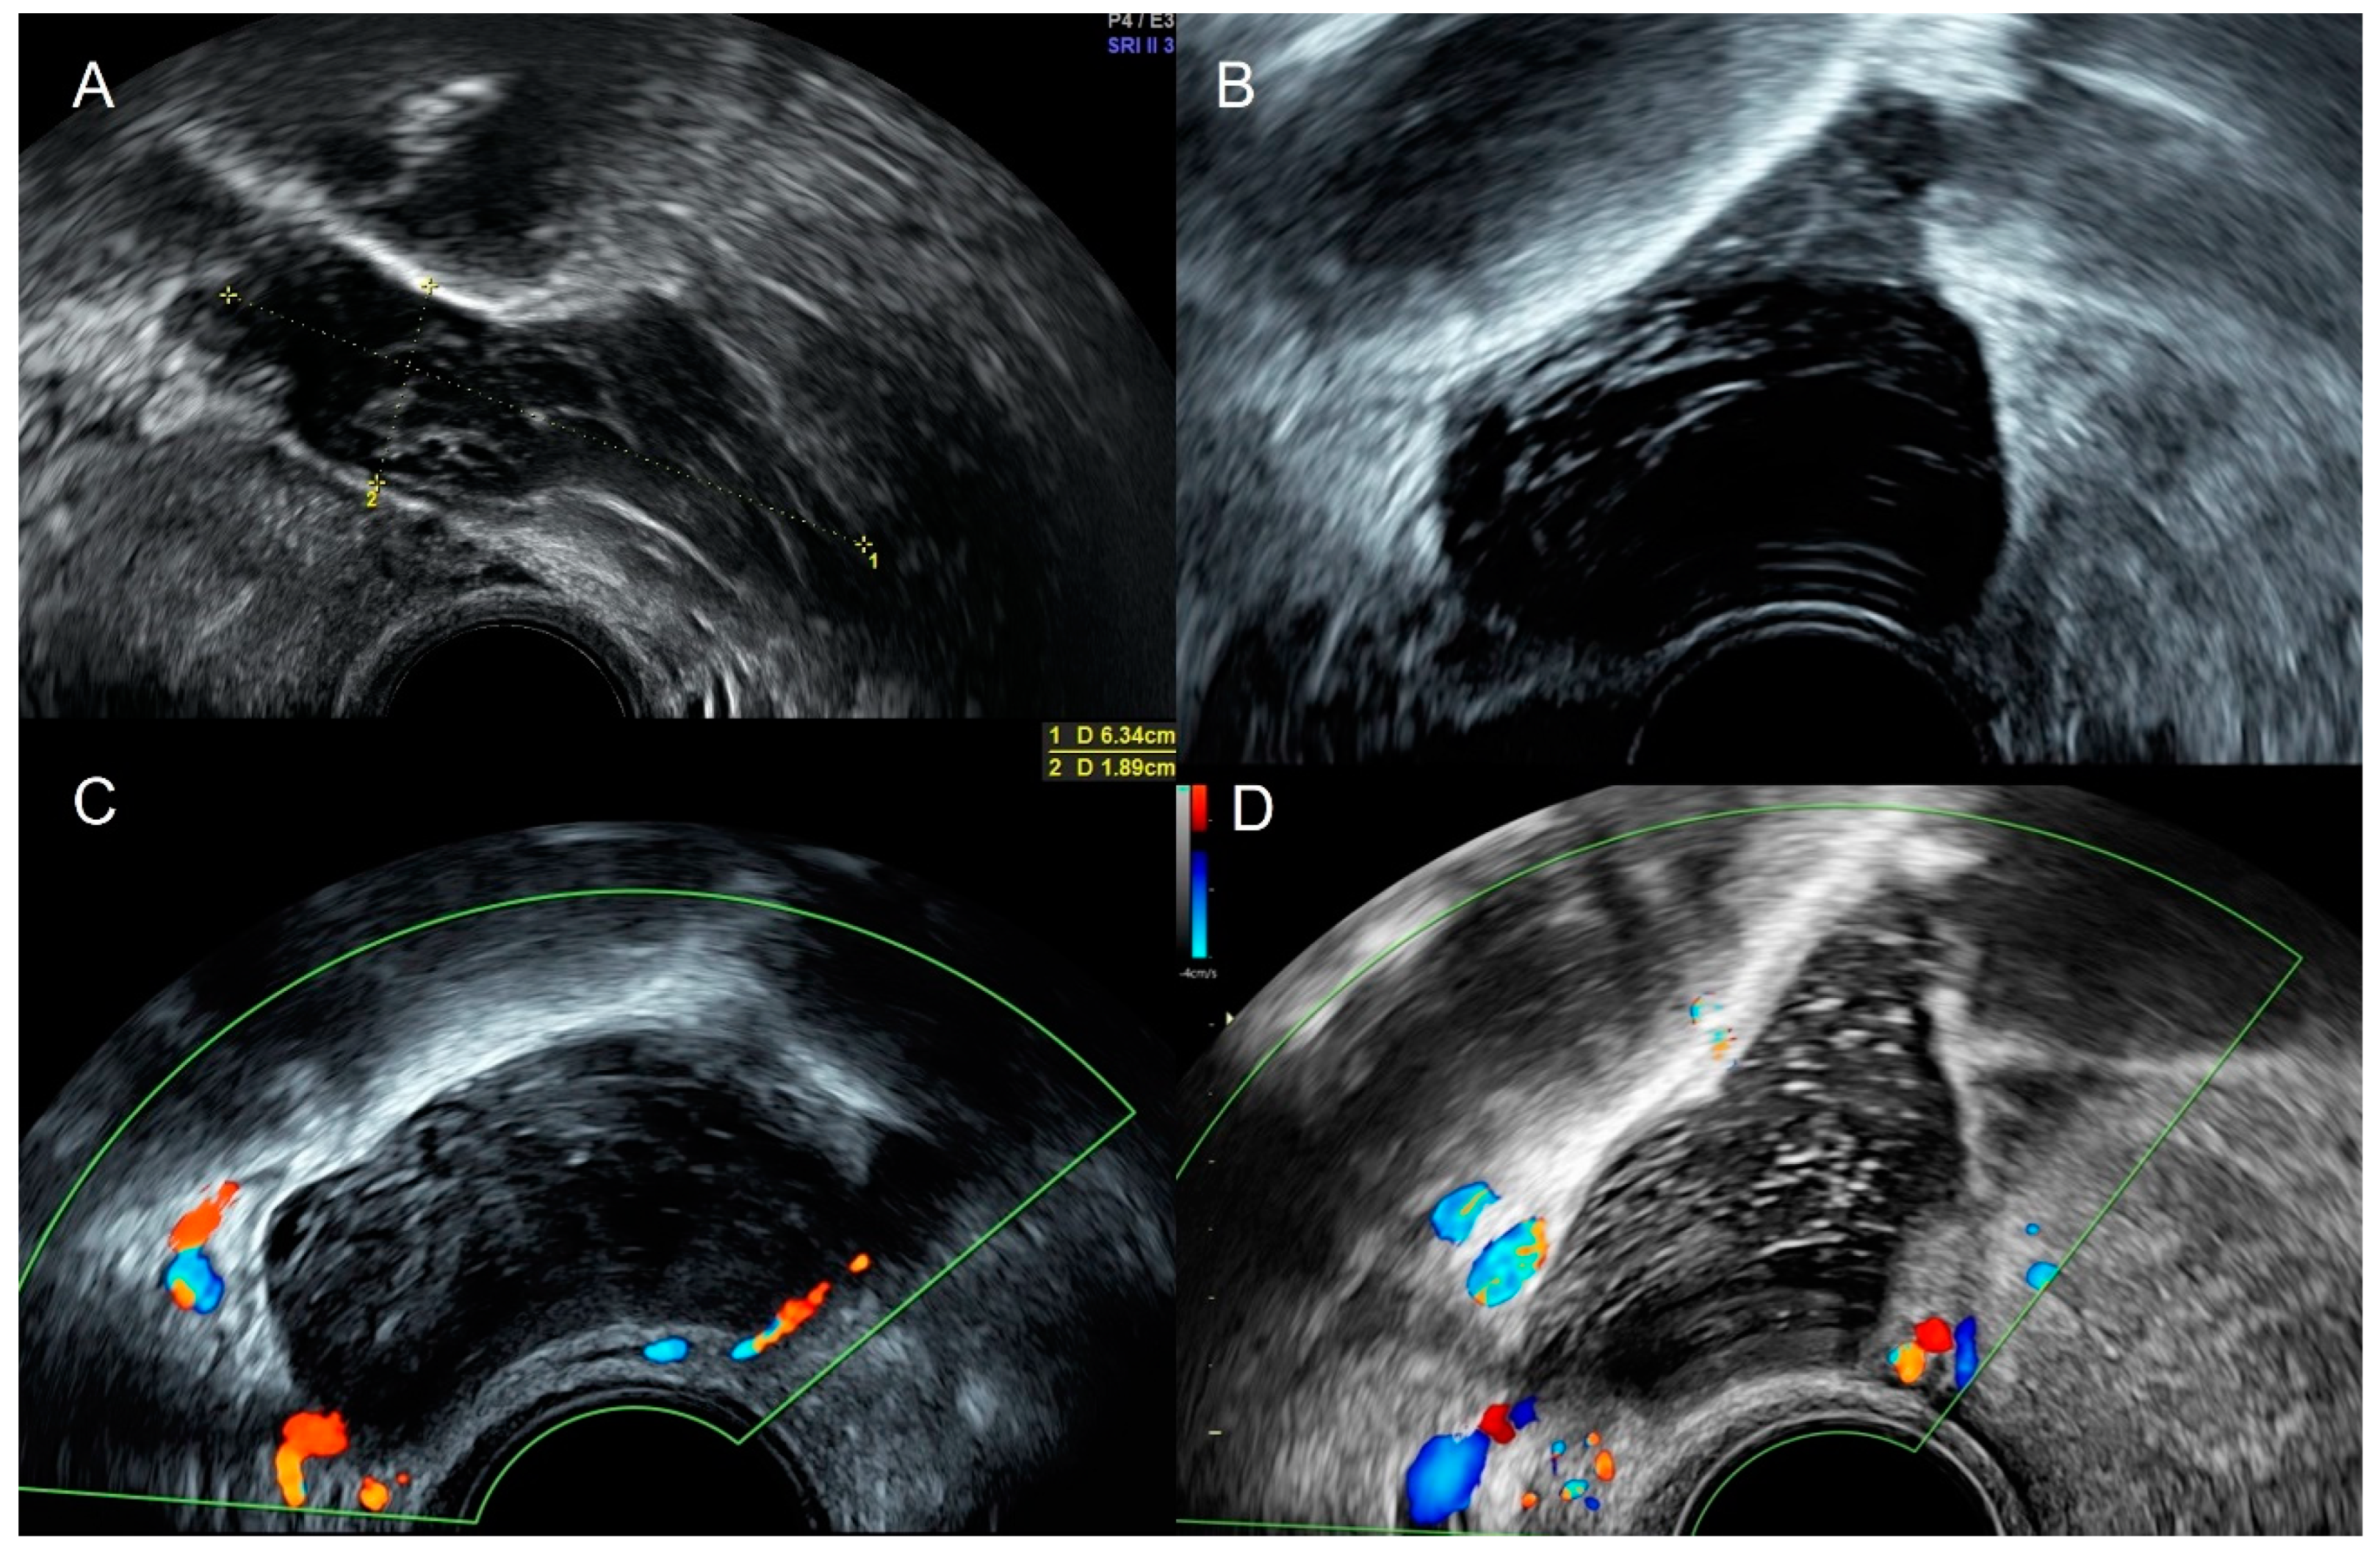

4.1. Pelvic Congestion